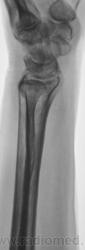

Травма.   Пациент направлен на рентгенографию лучезапястного сустава.